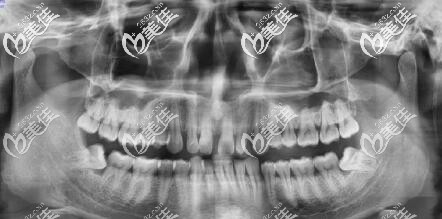

南昌男青年牙齿矫正之路,决定总是在一念间,我的牙齿是上门牙两颗之间有个较大的缝隙,而且整体往左偏颌,南昌维乐口腔做的隐适美矫正,拔四颗智齿。

在做矫正的检查时,居然发现我长了四颗智齿,还有两颗斜着长的,拔了智齿才做矫正。

我一共才23套牙套,初戴牙套的感觉,说话有一点点大舌头,后面就好了,还有前两天牙齿有酸软、很紧,每换下一幅牙套都有这个感觉,适应2天就好了。

等到戴第7副牙套的时候,牙齿就有变化了,原本缝隙较大的门牙,慢慢牙缝收起来了,也有一个很突的牙齿已经慢慢收进去了。